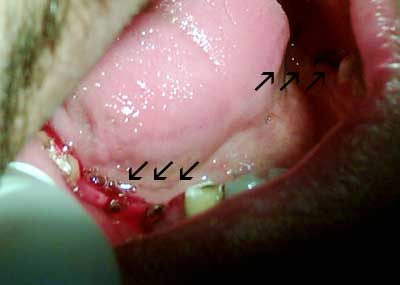

اسنان هشة جدا حيث ان السكيلنج يجرحها! لون الاسنان بني داكن